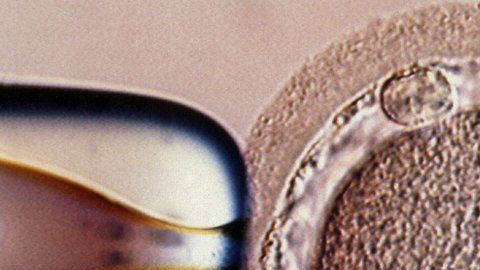

El bebé fue concebido mediante una técnica experimental.

El bebé fue concebido mediante una técnica experimental. Crédito: SPL

Para este procedimiento de fertilidad, llamado transferencia nuclear, se precisan dos óvulos: uno de la paciente y otro de la donante.

Al óvulo de la donante se le extrae el núcleo, que se destruye. Entonces se retira el núcleo del óvulo de la paciente y se pone dentro del óvulo de la donante.

A partir de ahí el óvulo resultante se fecunda y se implanta en el útero de la madre.